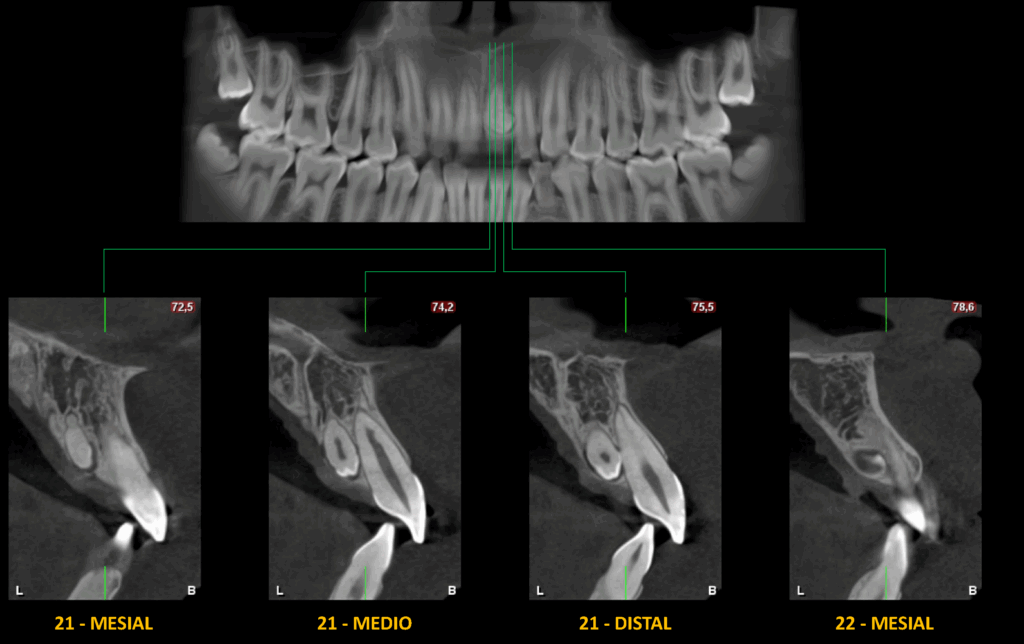

En el estudio complementario mediante tomografía computarizada de haz cónico (TCHC), se identifica una pieza dentaria supernumeraria (M) en posición palatina con respecto a la raíz de la pieza 21. La corona de esta estructura se encuentra en contacto directo con la superficie radicular de la pieza 21, como se evidencia en los cortes transaxiales.

CORTES TRANSAXIALES

- Pieza supernumeraria en línea media del maxilar superior (mesiodens).